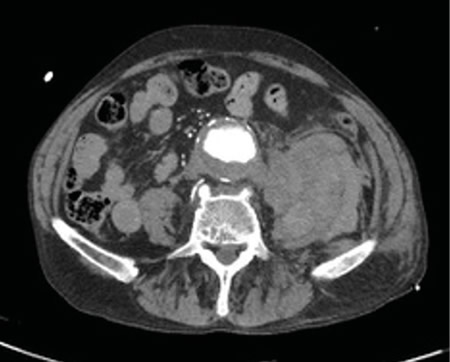

Figura 2